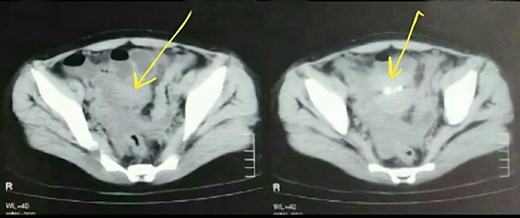

A 23-year-old woman presented to hospital complaining of chronic constipation that had started 2 month earlier. It was accompanied by colic abdominal pain and recurrent vomiting. Her general condition, appetite, urination, sleep and vital signs were all normal. As a history, she was admitted in a hospital previously with bowel obstruction due to sigmoid colon volvulus, but she was discharged after 2 days without any intervention. On physical examination, there was hypogastric pain without tenderness and visceral movements were slightly increased in the hypogastric and periumbilical regions. On radiology investigations, chest X-ray and echography of abdomen were all normal. CT scan showed multi-density formations in the left iliac region with a small amount of pelvic fluid (Fig. 1). The Barium Enema showed sigmoid colon elongation, without filling defects.